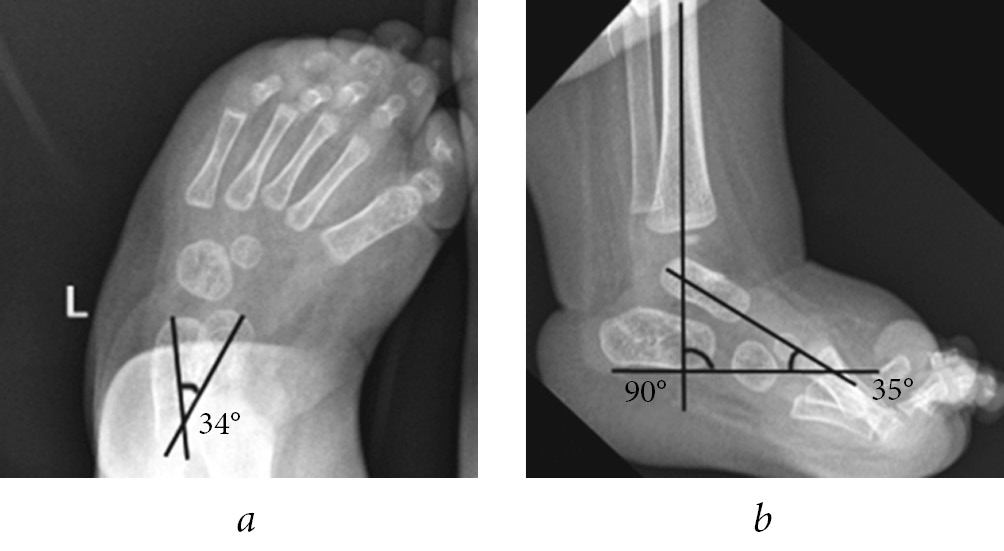

The illustration of some stages of treatment of patients of groups 1 and 2 with clubfoot with arthrogryposis according to the Ponseti method and radiographic data are presented in Figures 2 and 3.

Fig. 2. Appearance and radiograph of the foot in the lateral projection of patient K. with clubfoot with arthrogryposis from group 1: a — before the beginning of casting according to Ponseti; b — before achillotomy; c — after achillotomy; and d — after additional stage casting (two casts)